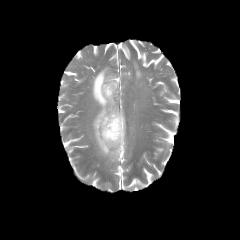

Glioma is a prevalent brain tumor that poses a significant health risk to individuals. Accurate segmentation of brain tumor is essential for clinical diagnosis and treatment. The Segment Anything Model(SAM), released by Meta AI, is a fundamental model in image segmentation and has excellent zero-sample generalization capabilities. Thus, it is interesting to apply SAM to the task of brain tumor segmentation. In this study, we evaluated the performance of SAM on brain tumor segmentation and found that without any model fine-tuning, there is still a gap between SAM and the current state-of-the-art(SOTA) model.